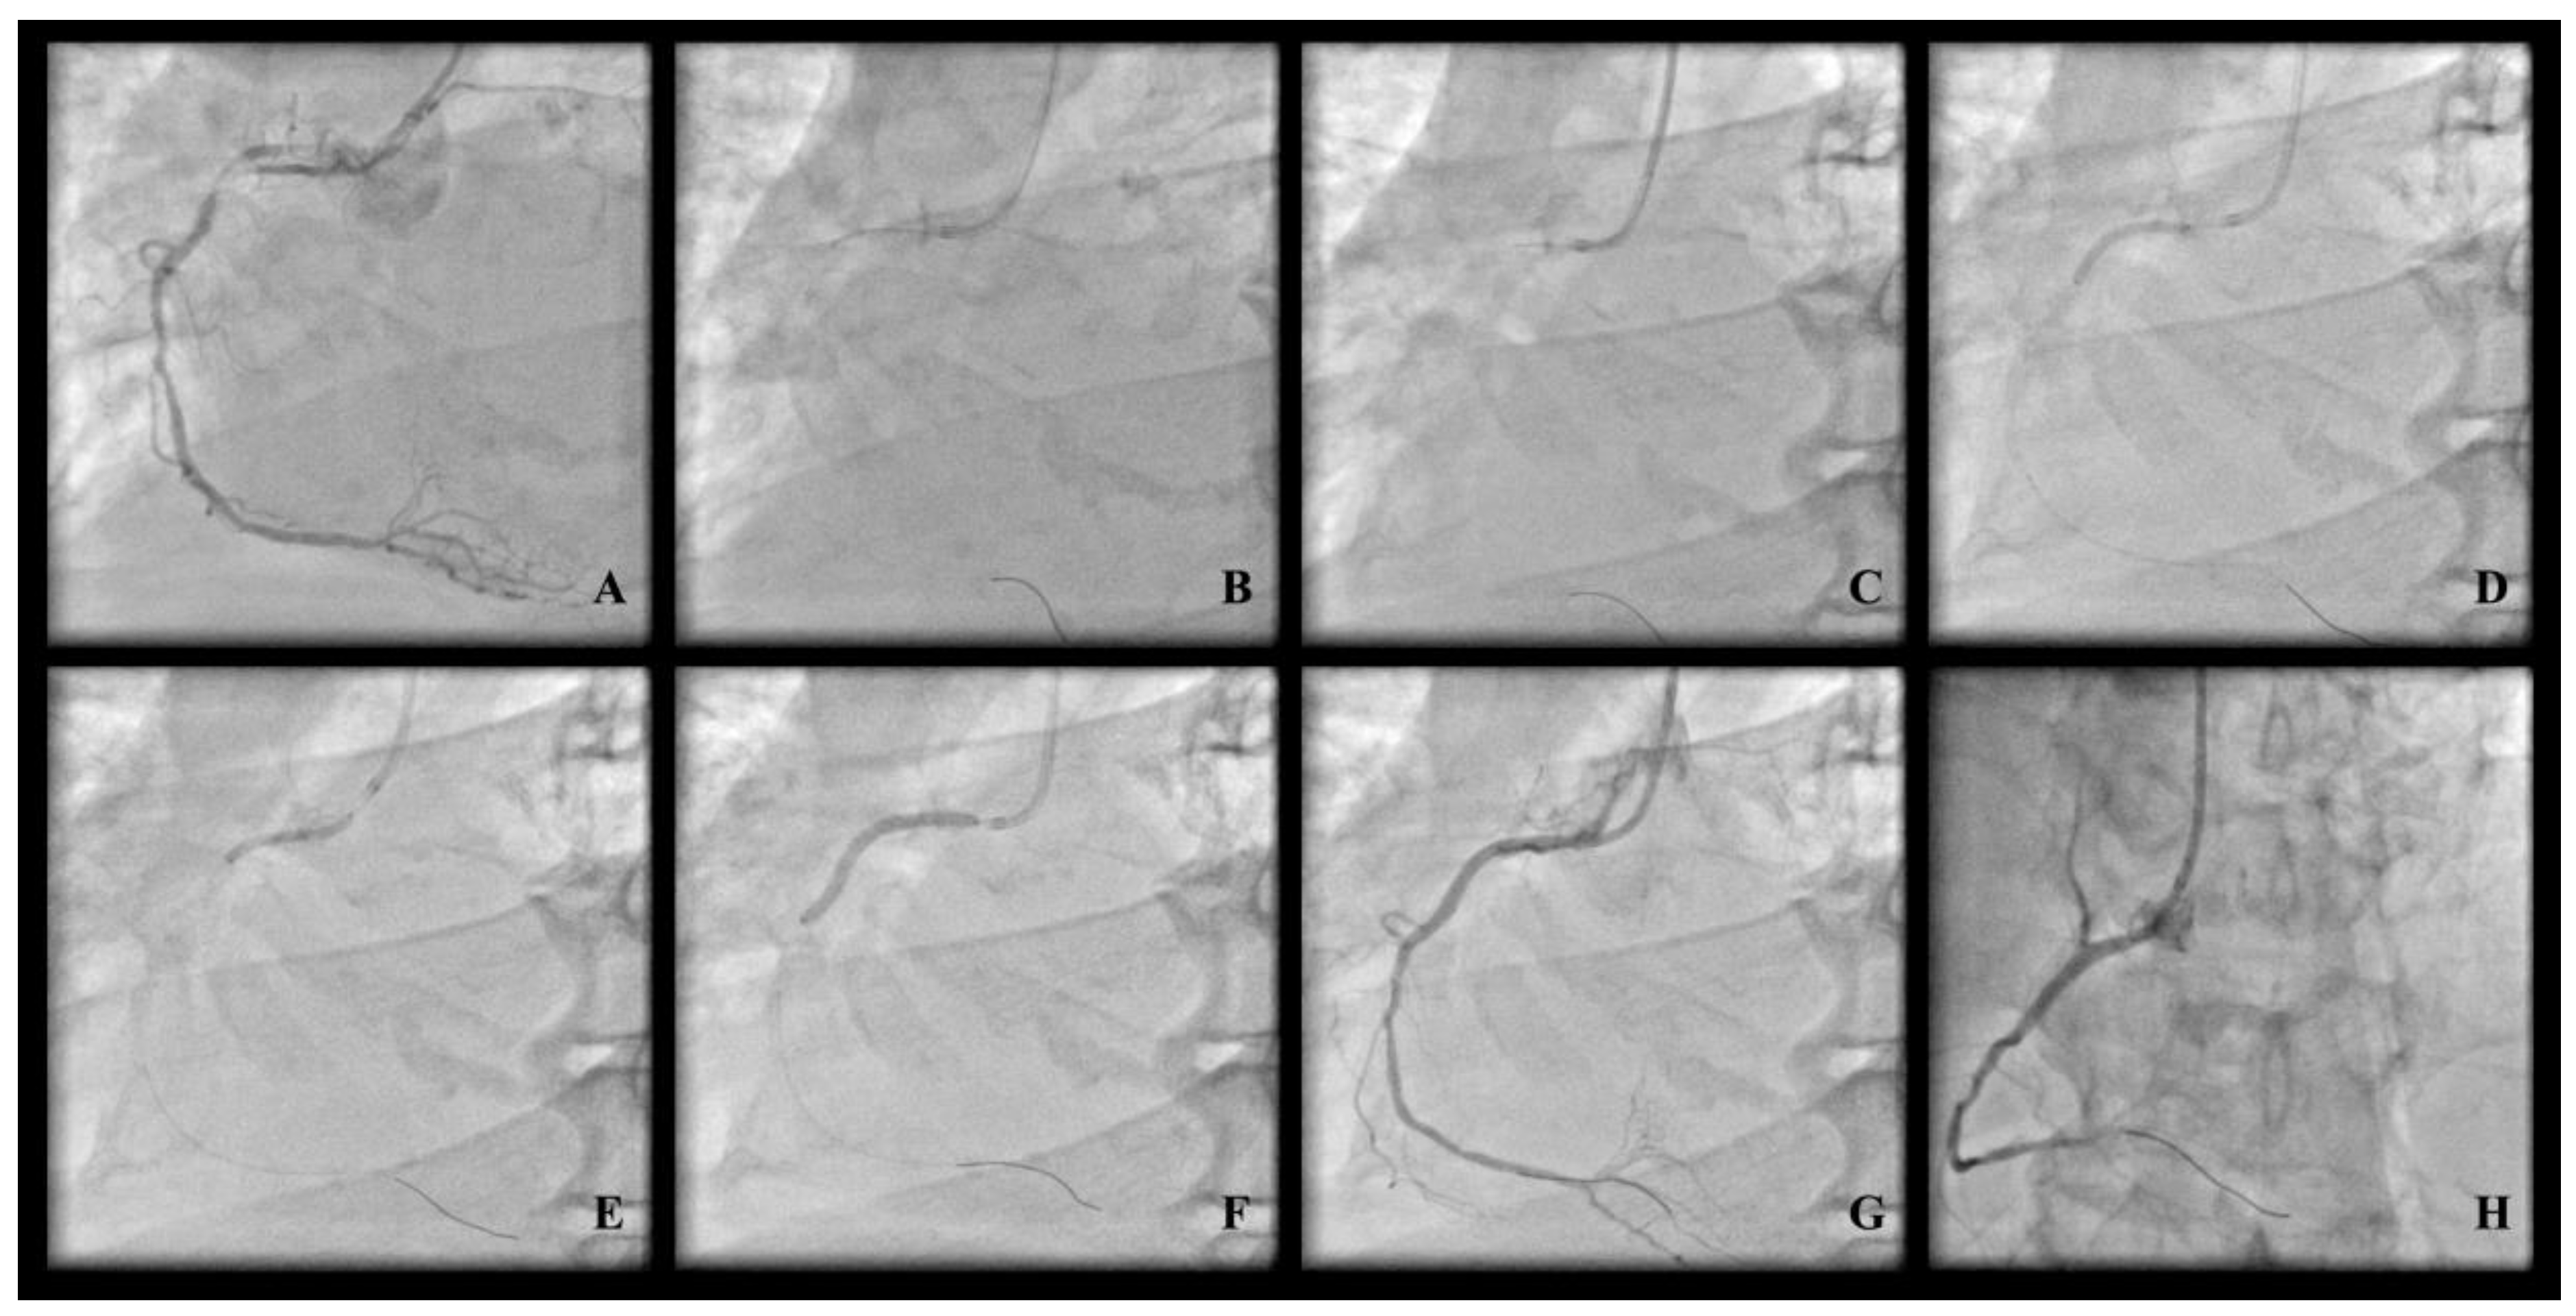

All procedural features (vascular access point, use of additional lesion preparation technique, stent implantation parameters, periprocedural pharmacological therapy, use of intravascular imaging support along with the left ventricular assist device) were left to the discretion of the operator. All OA procedures were started at OA at low speed (80,000 RPM) with additional passes at high speed (120,000 RPM) left to the discretion of the operator with strong encouragement to use high-speed mode only for a vessel diameter of at least 3.0 mm assessed based on coronary angiography. Despite prior stent implantation in the area of the target lesion, there were no other exclusion criteria regarding lesion anatomy (length, tortuosity, severity, or location). Figure 1 shows exemplary OA-PCI.

Figure 1.

Exemplary OA-PCI. (A) Proximal calcified “uncrossable” lesion; (B) orbital atherectomy crown engagement; (C) reverse orbital atherectomy ablation; (D) NC balloon predilatation; (E) NC balloon predilatation; (F) DES implantation; (G) final angiographic result; (H) final angiographic result.